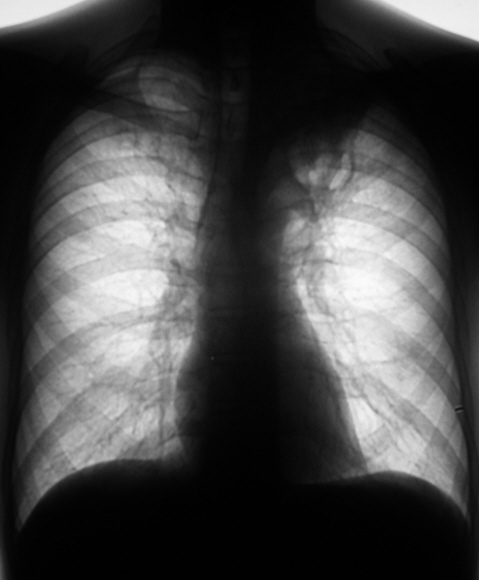

Пациент в 2007, 2008 гг. проходил профилактическую флюорографию - иллюстрации ниже. При прохождении флюорографиив 2009 г. "картинка" резко отличается от предыдущих.

1.Флюорограммы за 2007, 2008 гг. представлены, оценены, как норма.